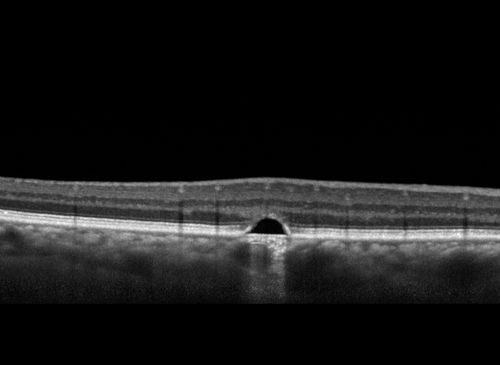

Polypoidal Choroidal Vasculopathy Left Eye

74 year old man with vision loss to 20/100 over a few months. He improved to 20/20 with Lucentis. The color and ICG show the polyps.

Polypoidal Choroidal Vasculopathy Left Eye - Visible on Color Images